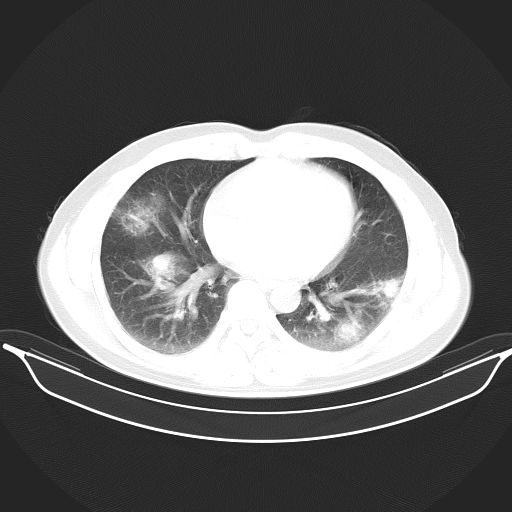

标题: CT25490:男,40岁,体检发现;无其它不适。 [打印本页]

标题: CT25490:男,40岁,体检发现;无其它不适。

倾向于结核

多考虑结核。

考虑结核

考虑肺霉菌病。

没有结核的诊断依据。

考虑右下肺周围性肺癌并肺内多发转移,纵隔淋巴结转移!

支持 !考虑右下肺周围性肺癌并肺内多发转移,纵隔淋巴结转移,(气管前腔静脉后,隆突下,主动脉弓下都有了)

1、均为转移,原发灶不在肺内。2、肺癌肺转移。